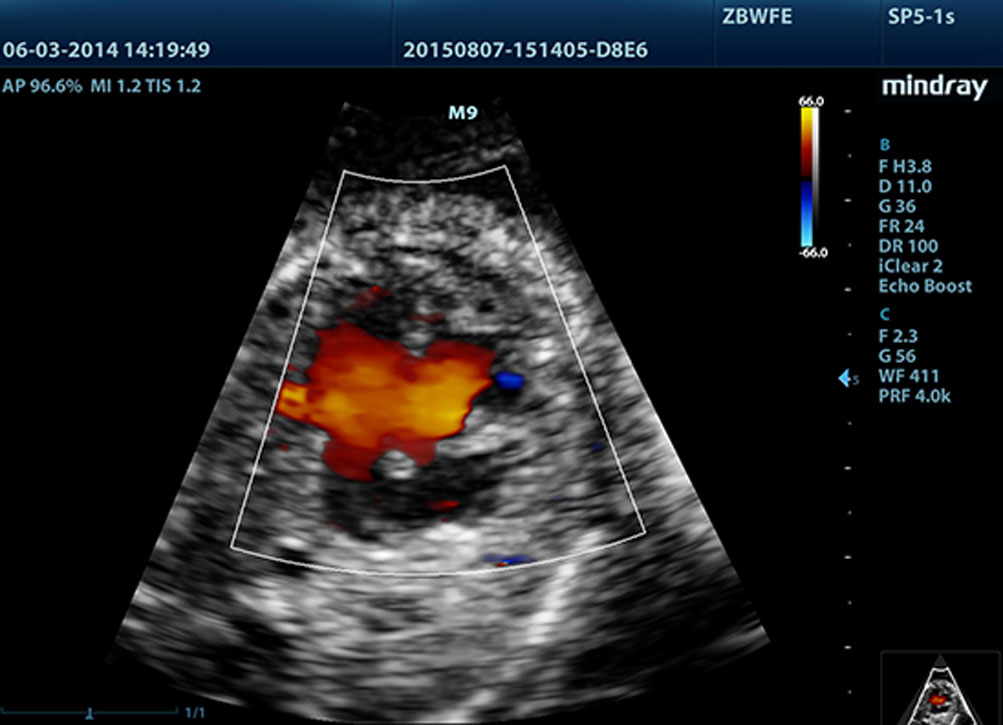

LVO with Stress Echocardiography

M9ŌĆÖs premium capabilities allow for LV opacification during stress, enhancing discrimination between myocardial tissue and blood pool, providing better visualization of the endocardial surface. Stress Echo feature on M9 includes a complete package for pharmacological stress and exercise stress echo. The package is supported by a flexible reporting system that can be optimized for your individualistic needs.